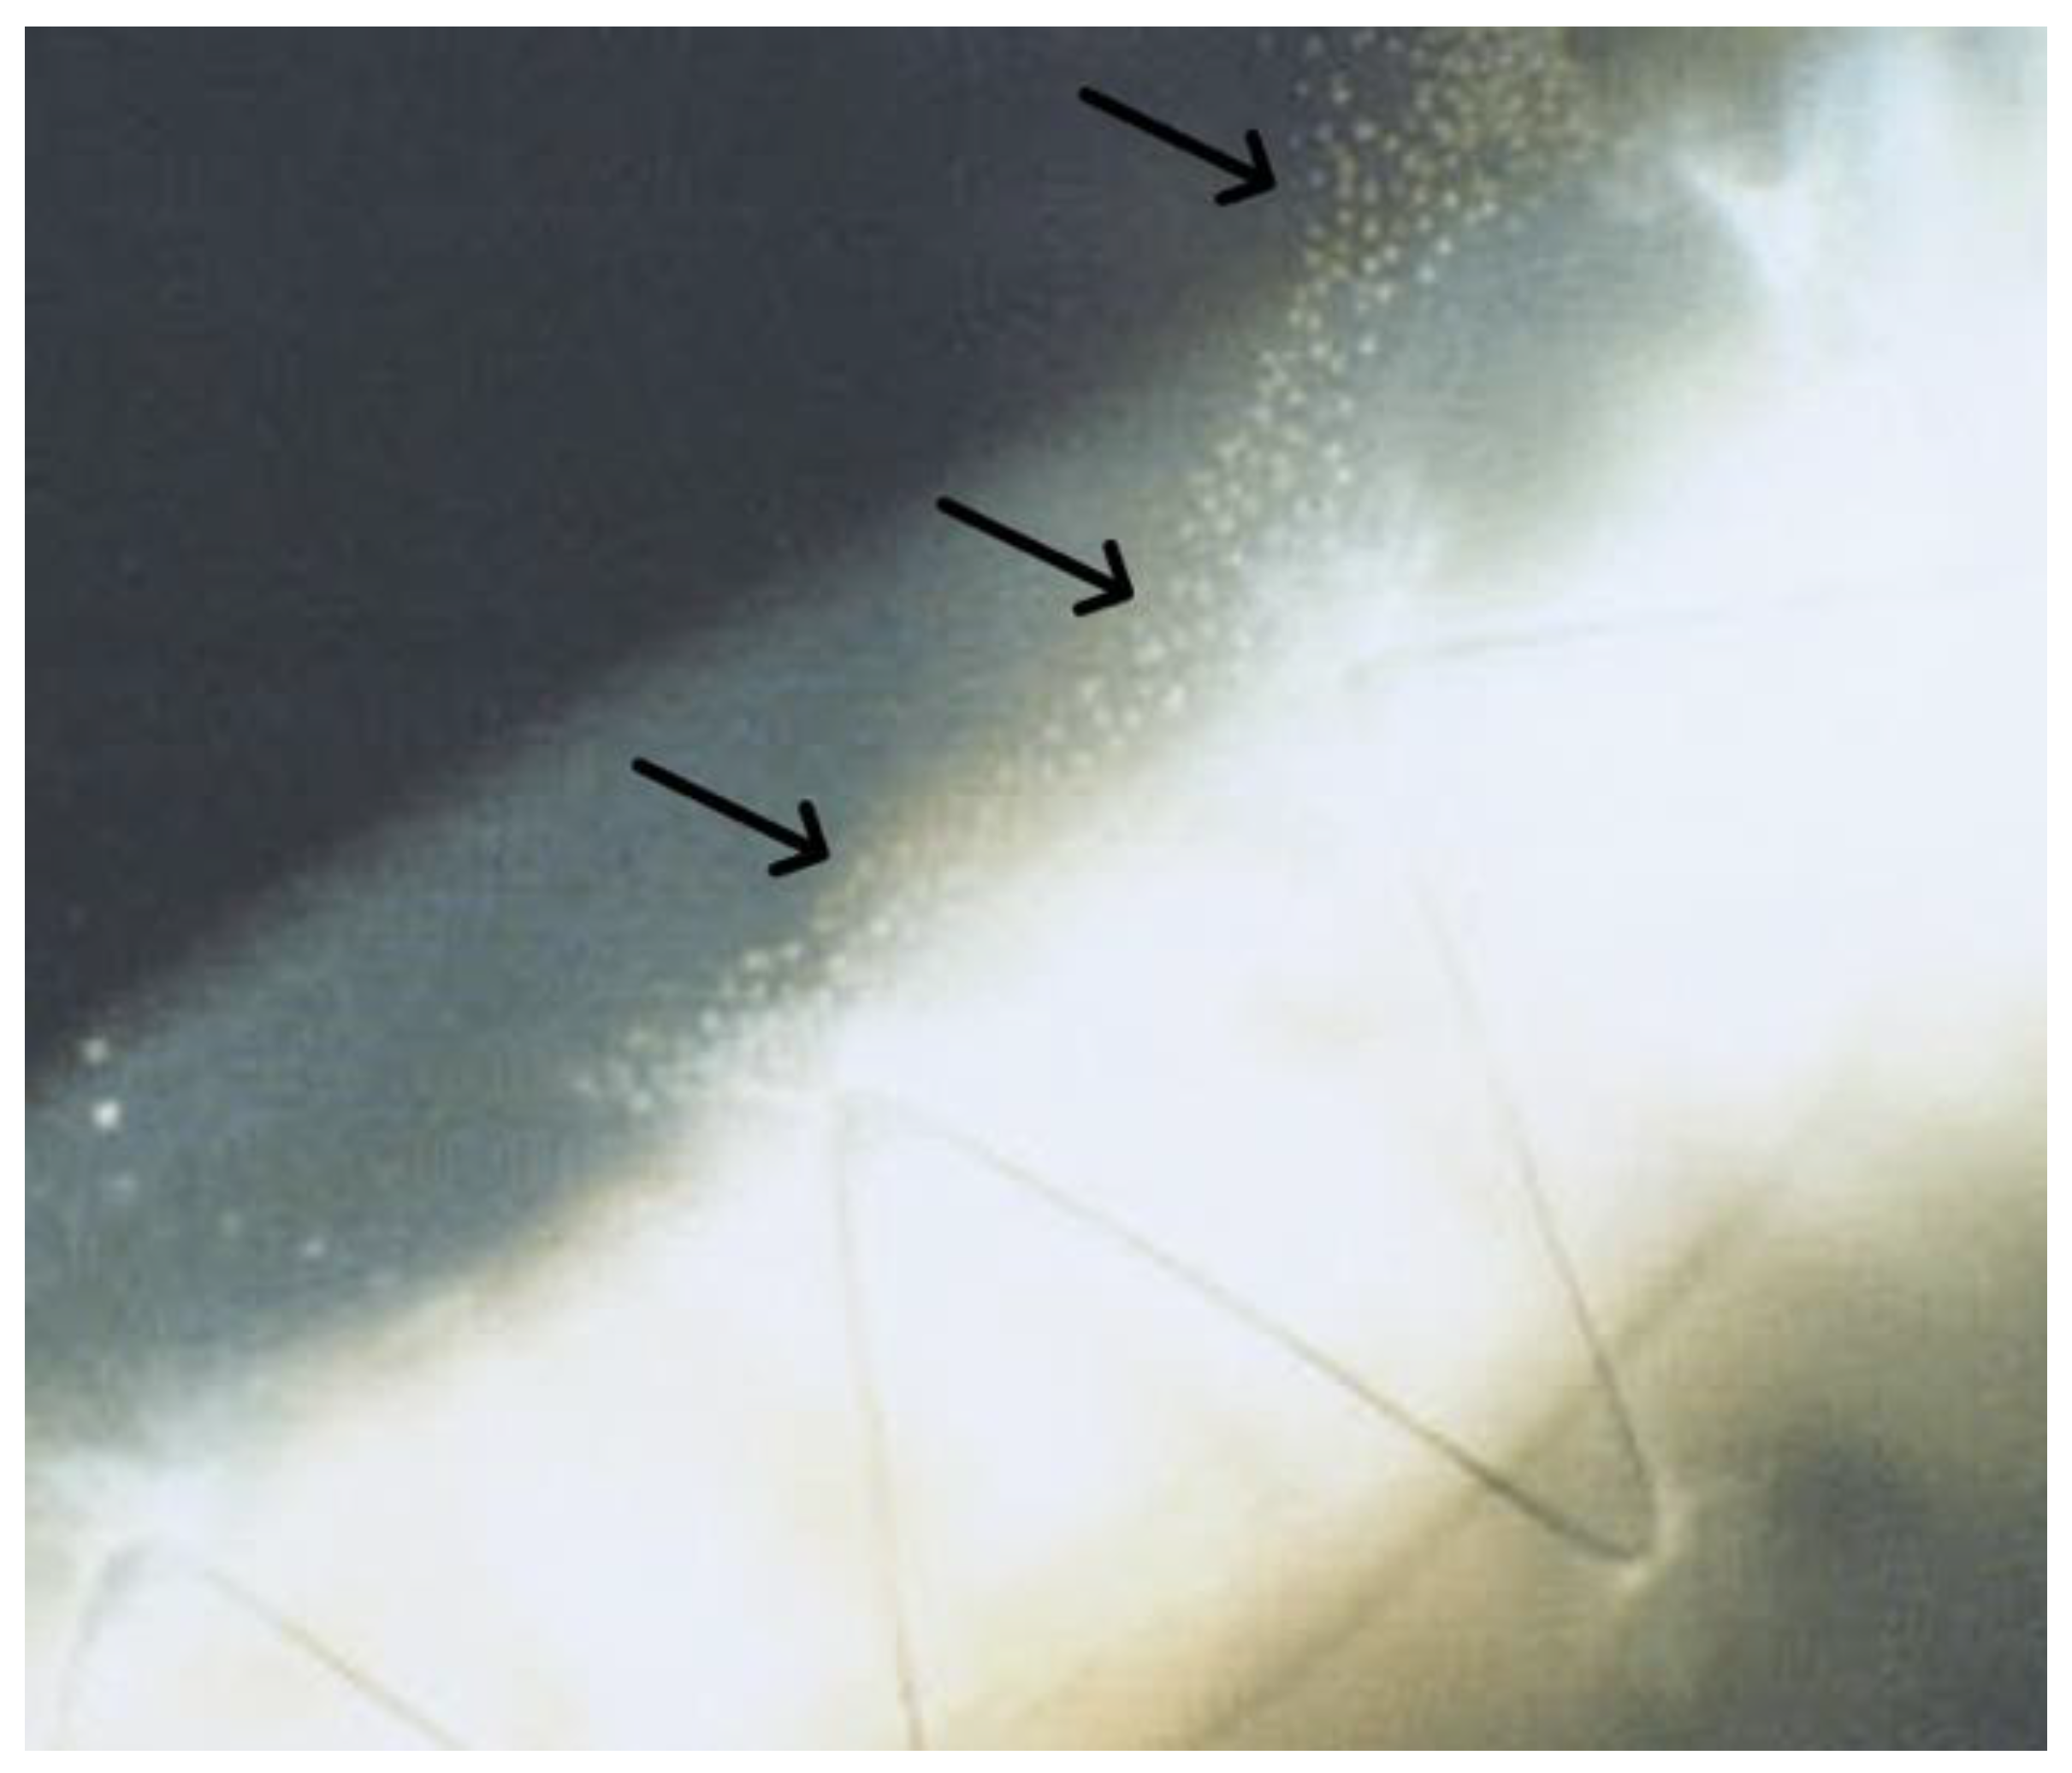

2.1. Slit Lamp Biomicroscopy

2.2. Keratoscopy